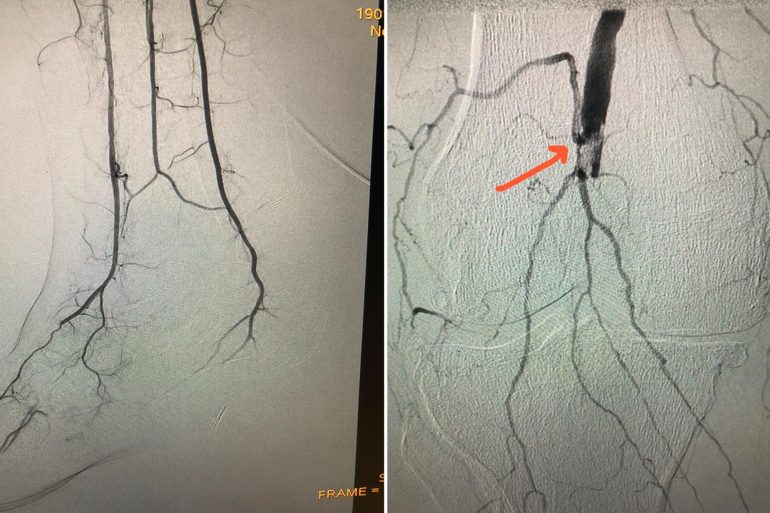

أنقذ فريق طبي بمستشفى د. سليمان الحبيب بالتخصصي مريضاً يبلغ من العمر “84” عاماً من بتر القدم اليسرى المصابة بجلطة... Read More